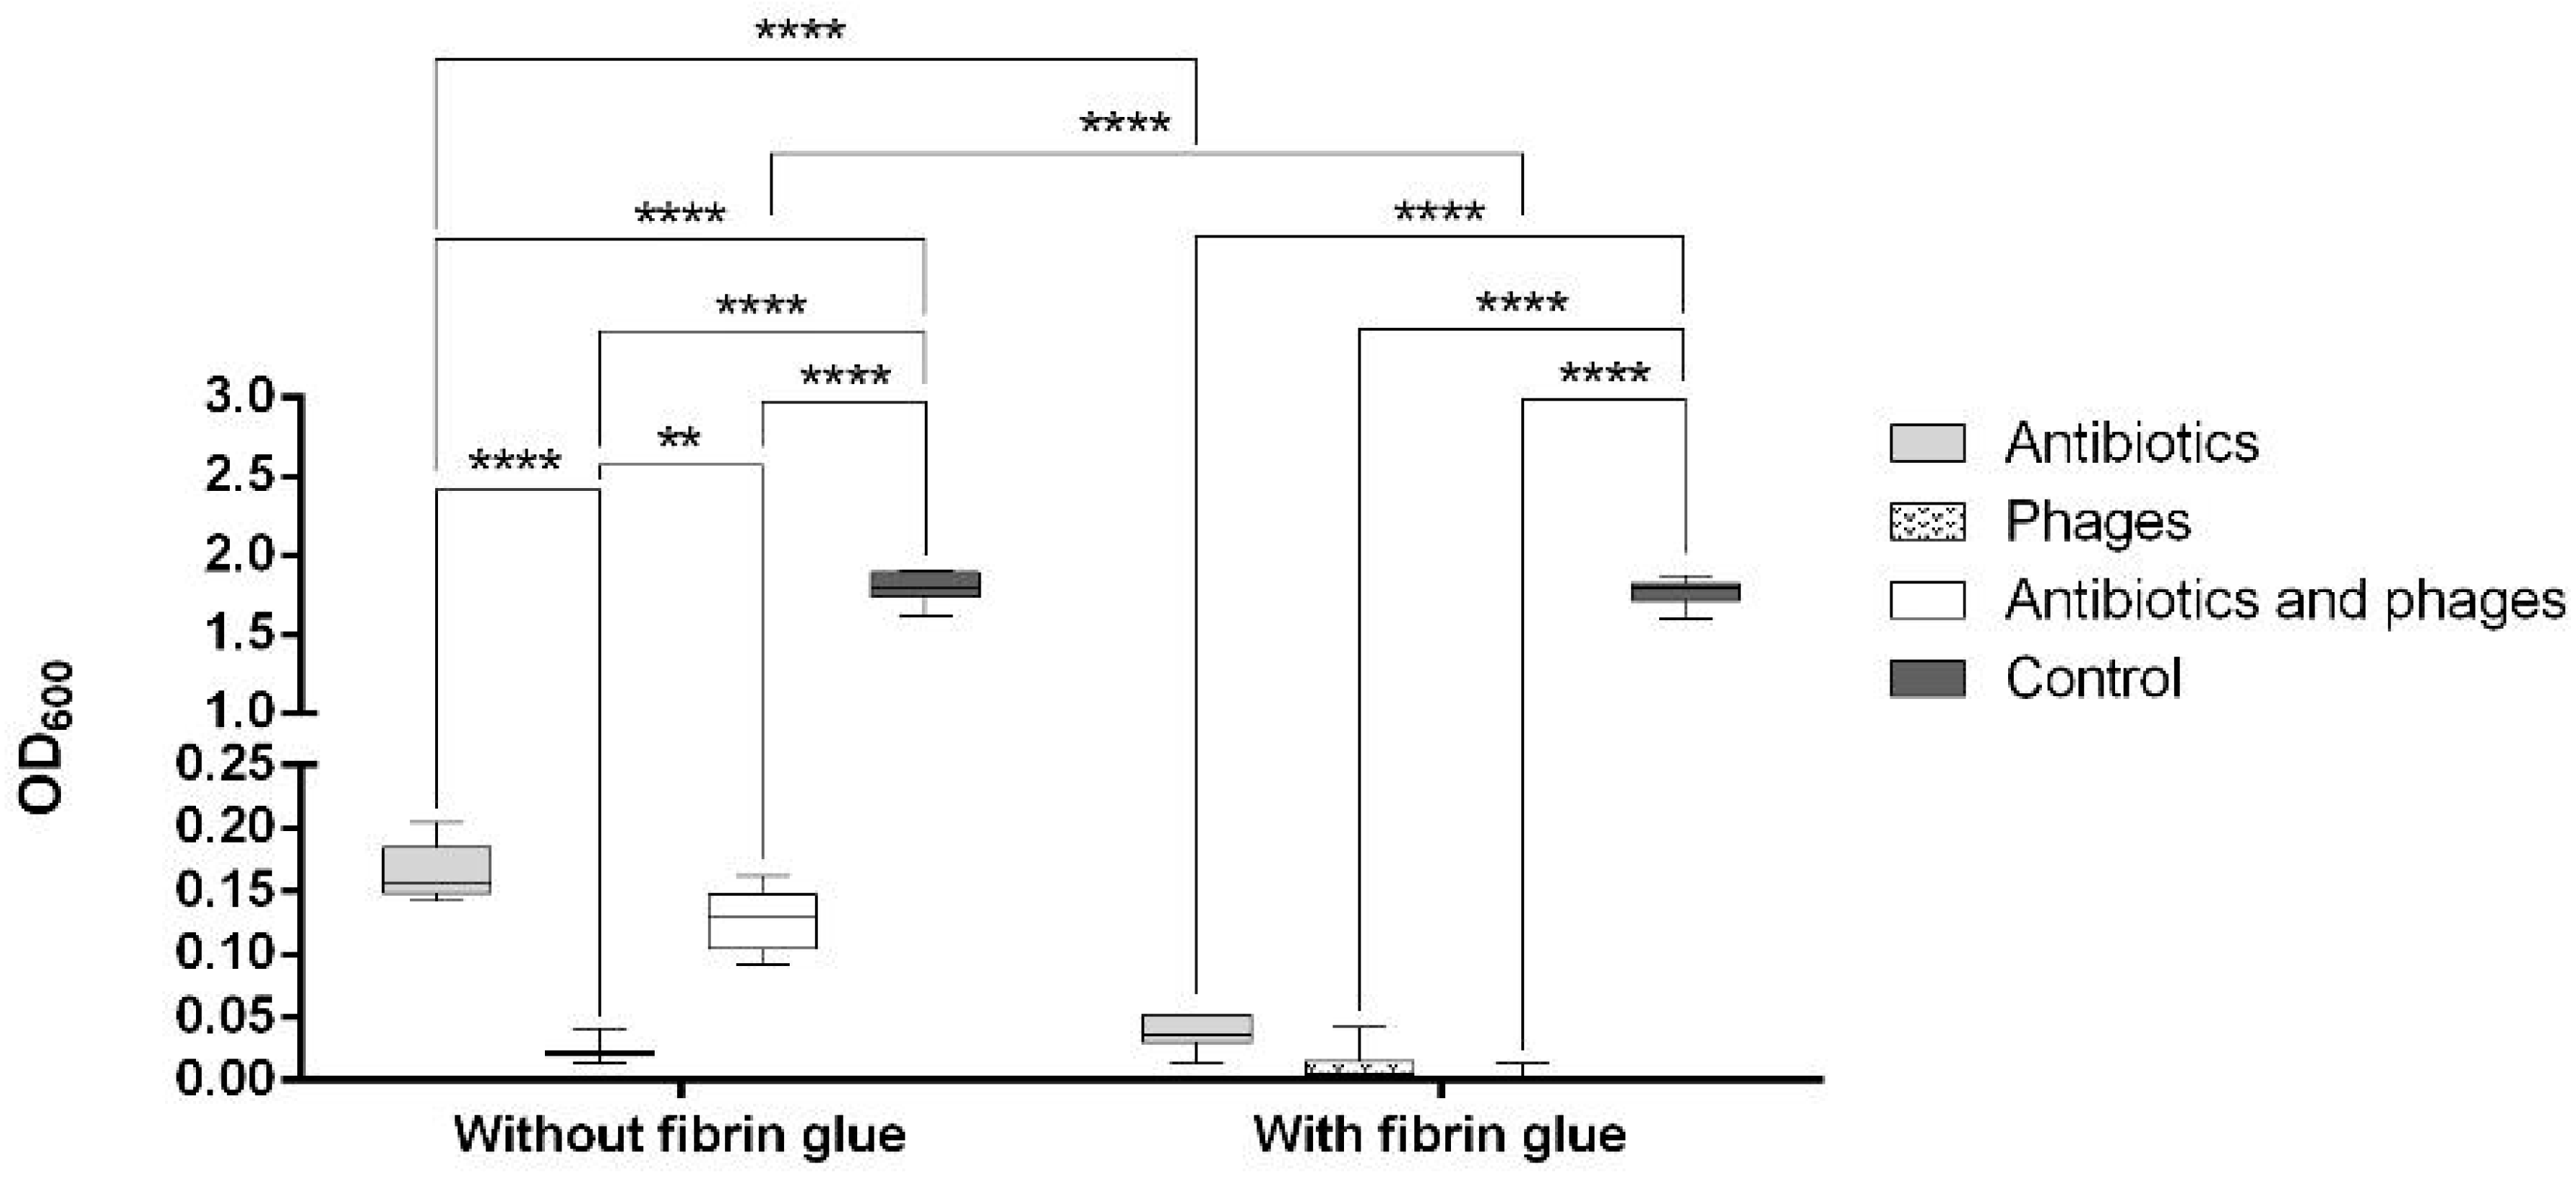

2.2. Antibacterial Loads of Graft Samples

2.2.1. Uncoated Grafts

2.2.2. Coated Grafts

2.3. Antibacterial Activity against Single Contamination

2.3.1. Activity against Staphylococcus aureus

2.3.2. Activity against Escherichia coli